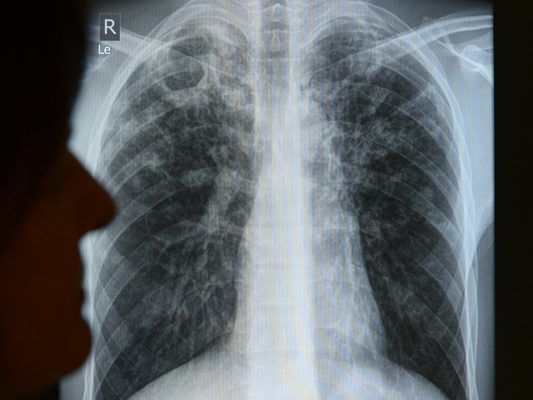

Tuberkulose ist eine Infektionskrankheit, die Ansteckung erfolgt über eine sogenannte Tröpfcheninfektion. Zur Behandlung werden Antibiotika eingesetzt.